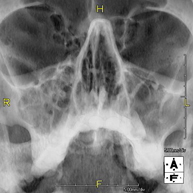

- Paranasal Sinuses X-ray

This technique uses X-ray rendered imaging for examining the paranasal sinuses. Indicated for: headache, chronic cough.